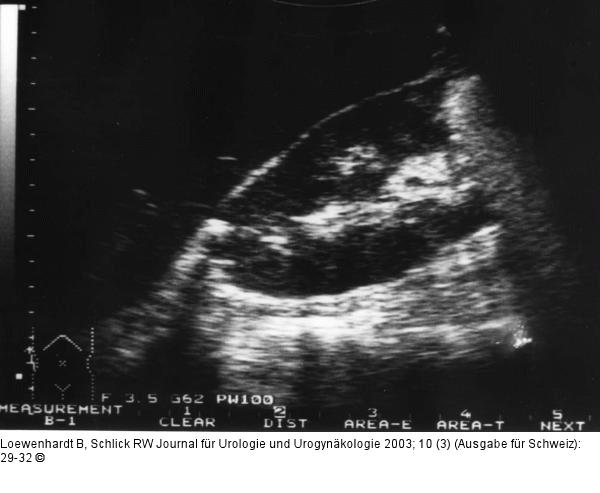

Abbildung 5: Emphysematöse Pyelonephritis Sonographie der rechten Niere. Echogene Formation am Oberpol mit Schallschatten. |

Abbildung 5: Emphysematöse Pyelonephritis

Sonographie der rechten Niere. Echogene Formation am Oberpol mit Schallschatten. |